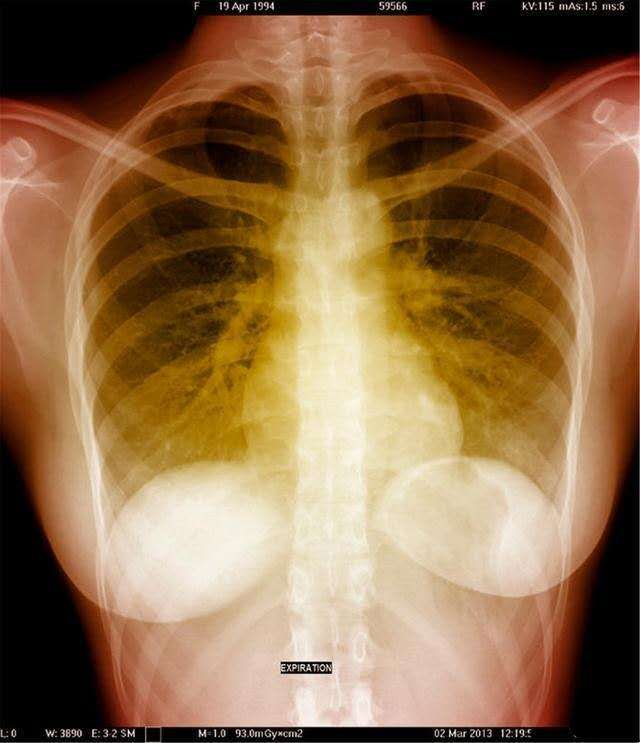

他的临床表现为反复发作的呼吸系统感染伴排痰性咳嗽,喘鸣音及呼吸困难。CT表现为支气管扩张症,通常累及所有的肺叶,但是倾向于肺上叶最严重。